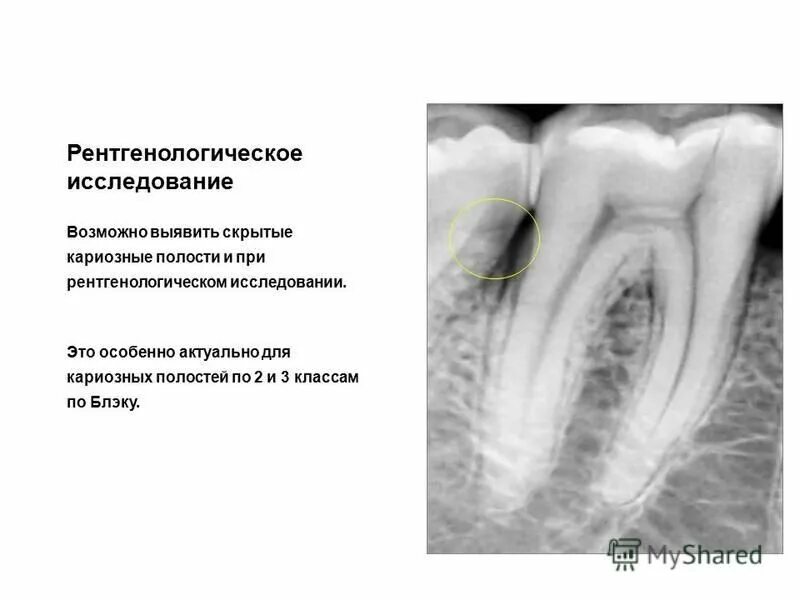

Кариозная полость сообщается с полостью зуба